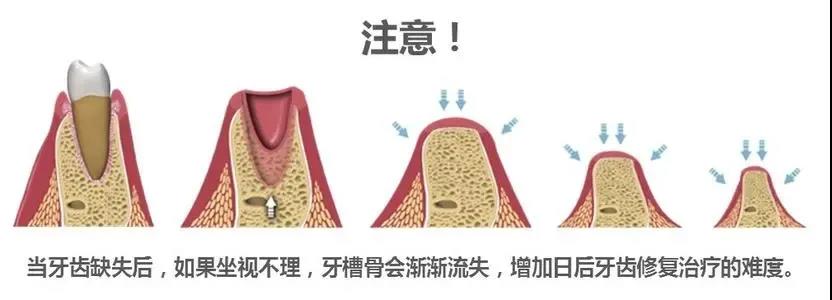

如果你有缺牙,不妨及时种牙止损,避免口腔环境随着时间变得复杂,增加种牙难度与费用。 缺牙久了,种是可以种,但过程会比较坎坷。因为长期缺牙,可能会导致: 01 咬合关系破坏... 详情

牙齿三缺一,不补会怎样? 危害一:临牙松动,又掉两颗 牙齿缺失后,相邻的牙齿会因为没有固定的依靠,向缺牙间隙倾斜,时间长了会造成周围邻牙的松动,致使全口牙齿的正常功能... 详情

缺牙久了,种是可以种,但过程会比较坎坷 所以在缺牙之后就一定要及时去补牙 否则拖长了时间真的没有好处! 咬合关系破坏,需要咬合重建 对颌牙伸长、邻牙倾倒、余牙移位时间越... 详情